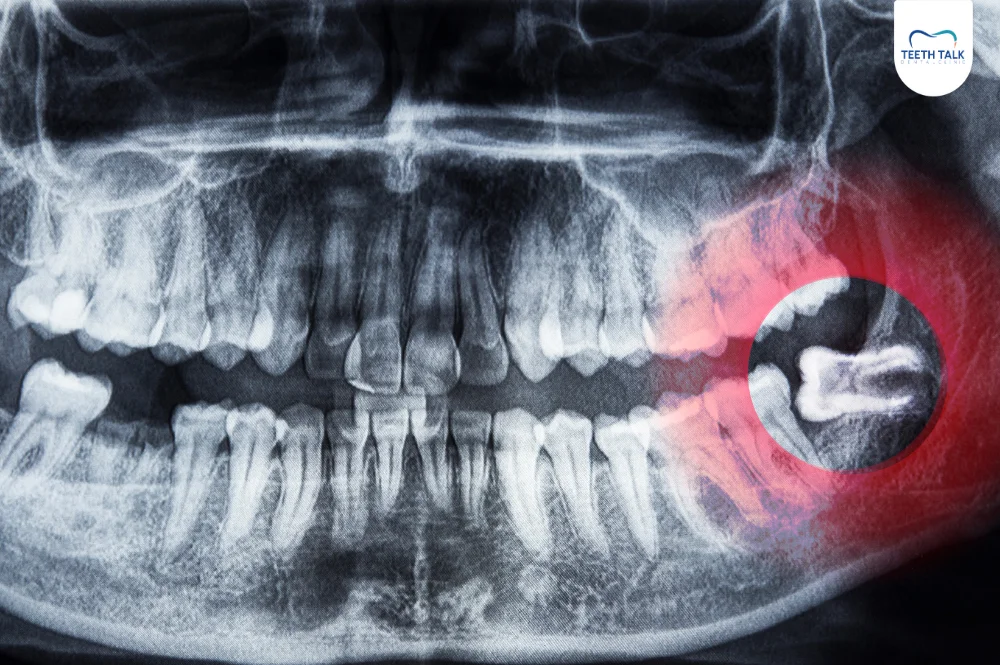

ถึงแม้จะไม่มีอาการผิดปกติใด ๆ การตรวจเช็กว่าคุณมีฟันคุดหรือไม่ด้วยวิธีที่แม่นยำที่สุดคือการเข้าพบทันตแพทย์เพื่อทำการเอกซเรย์ (X-ray) ช่องปาก เพราะภาพเอกซเรย์จะสามารถแสดงให้เห็นฟันคุดที่ฝังตัวอยู่ใต้กระดูกได้อย่างชัดเจน ทำให้ทันตแพทย์สามารถประเมินตำแหน่ง ทิศทาง และผลกระทบที่อาจเกิดขึ้นกับฟันซี่ข้างเคียงได้อย่างแม่นยำ

ฟันคุดที่ขึ้นเอียงหรือแนวนอน ชนฟันข้างเคียง

เป็นกรณีที่พบได้บ่อยที่สุด ฟันคุดที่ขึ้นในลักษณะนี้จะสร้างแรงดันไปที่รากของฟันกรามซี่ที่อยู่ข้างหน้าอย่างต่อเนื่อง ซึ่งเป็นความเสี่ยงสูงที่อาจทำให้รากฟันซี่นั้นละลาย หรือเกิดฟันผุในบริเวณซอกฟันที่ทำความสะอาดไม่ได้